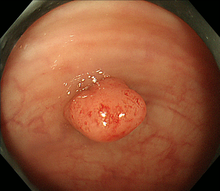

図 大腸ポリープ

1)内視鏡的ポリープ切除術(ポリペクトミー)

大腸に隆起したポリープを認めた場合、ポリープの茎の部分に、内視鏡を通して通電ワイヤー(スネア)を掛け、ポリープを締め上げて高周波電流で切除します。高周波で切除することにより、切除した部位に熱凝固という作用が起きて止血できます。大腸粘膜には知覚神経がないため切除時には痛みは感じません。ポリープの大きさや形状によって1日から数日間の入院が必要です。